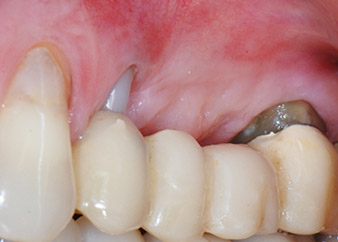

Un mes después, en el día de la intervención, el dolor y la inflamación se habían reducido al mínimo en la pieza 24, pero seguía habiendo una movilidad de clase II de Miller. Después de la apertura de los colgajos y de la limpieza del tejido infectado periapical y perirradicular, la extensión del defecto óseo quedó evidente (figuras 2 y 3).

En la raíz bucal, faltaba todo el hueso vestibular y distal. Básicamente, la fijación se limitó a la raíz palatal, lo que corroboró el mal pronóstico preliminar. La pieza 27 también mostró una fijación horizontal reducida (figura 12) y una rarefacción apical mínima (figura 1), si bien sin síntomas clínicos.